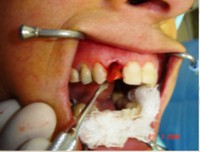

Carga Imediata após exodontia atraumática

Fatos interessantes pertinentes a este caso:

- Extração imediata

- Implante imediato

- Carga imediata

- Coroa protética cerâmica imediata

- Aplicação da cerâmica de baixa fusão direto sobre o pilar